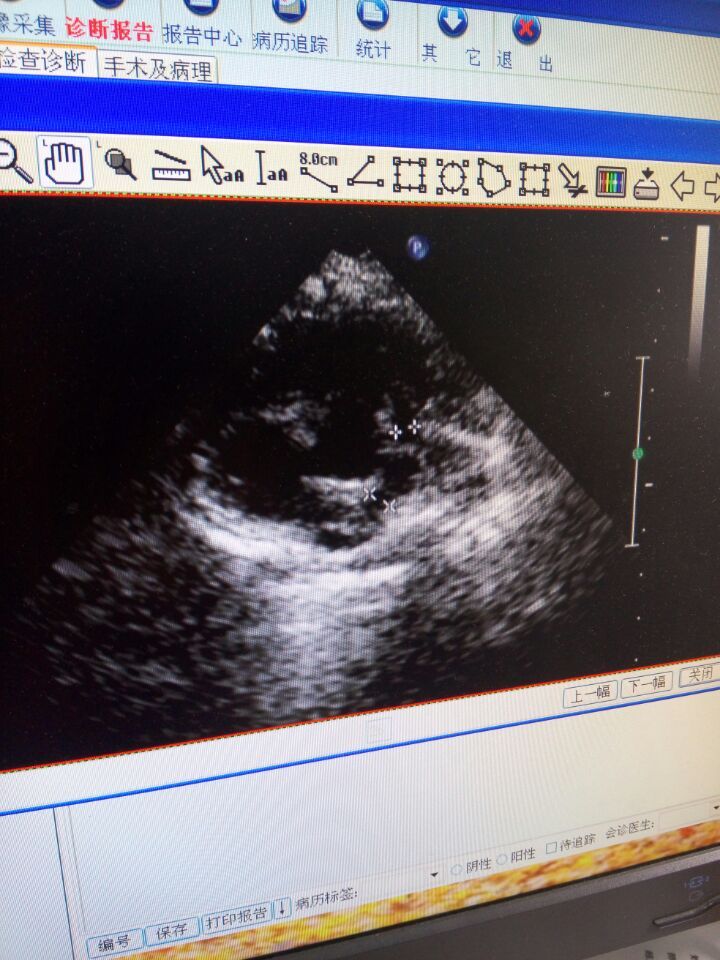

平时哭出现紫绀,没力气吃奶,易出现喉响、出汗,活动是明显,去医院做了B超肺动脉狭窄厉害才约0.3cm,主动脉骑跨约50%,室缺1.7cm,右室大,悲伤至极,想问问专家现在能手术吗?想去上海儿童医学中心手术?但农村的没出过门,希望得到好心人帮助